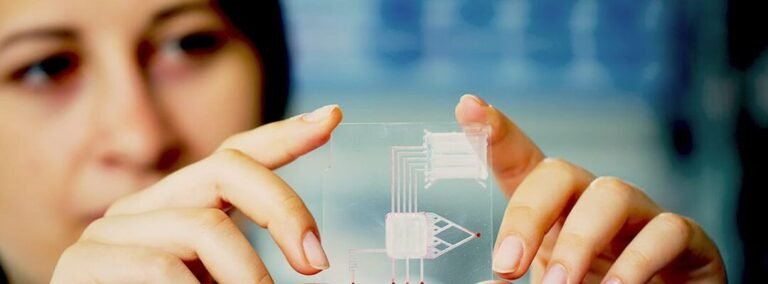

Las microagujas bioinspiradas para inyecciones sin dolor representan un avance revolucionario en el campo de la administración...